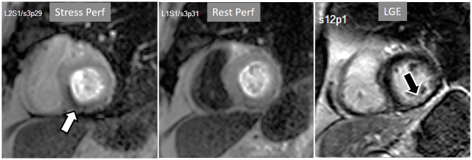

Particularly important, in practice, is the issue of perfusion studies in patients with previous MI. In theory, a basal rest perfusion study should exhibit a reduced signal intensity in the infarcted area, as is the case in the acute phase of a large transmural MI (Fig. 14A). However, not infrequently, the presence and extent of a rest perfusion defect does no correlate with the actual area of necrosis in either, acute (Fig. 14B) or chronic MI (Fig. 15). Signal intensity in areas of previous MI is thus, not dependent merely on the presence of scar tissue, but some other factors lead to differences in CA concentration between MI and remote regions and, in this sense, rest perfusion CMR cannot be equated to SPECT studies, where rest defects are directly related to the presence of infarcted myocardial tissue not amenable to radiotracer uptake [45].

Fig. 14.Rest perfusion after acute myocardial infarction. (A) Frames from different sequences in a case of acute MI showing, from left to right, (1) gross transmural defect at the rest perfusion study (arrow); (2) signs of regional myocardial edema at STIR T2, with a mid-line low intensity region which proves to be due to (3) intramural hematoma at T2* sequence; (4) persistence of hypoperfusion at Early Gadolinium Enhancement (EGE); and (5) transmural anteroseptal necrosis with a subendocardial area of microvascular obstruction (arrow). (B) The same series of sequences in another patient with AMI showing (1) mild subendocardial defect at rest (arrow); (2) regional edema; (3) absence of hematoma at T2*; (4) lack of persistent defect at EGE; and, finally, (5) a transmural infero-lateral LGE (arrow) without microvascular obstruction.

Fig. 15.Rest perfusion in chronic myocardial infarction. Basal rest perfusion study showing a reduced subendocardial septal defect (asterisk) at the apical septum in a patient with an extensive old anteroseptal MI evidenced at LGE.